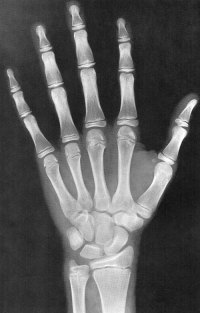

Sexo Feminino

Recém-Nascido

3 meses